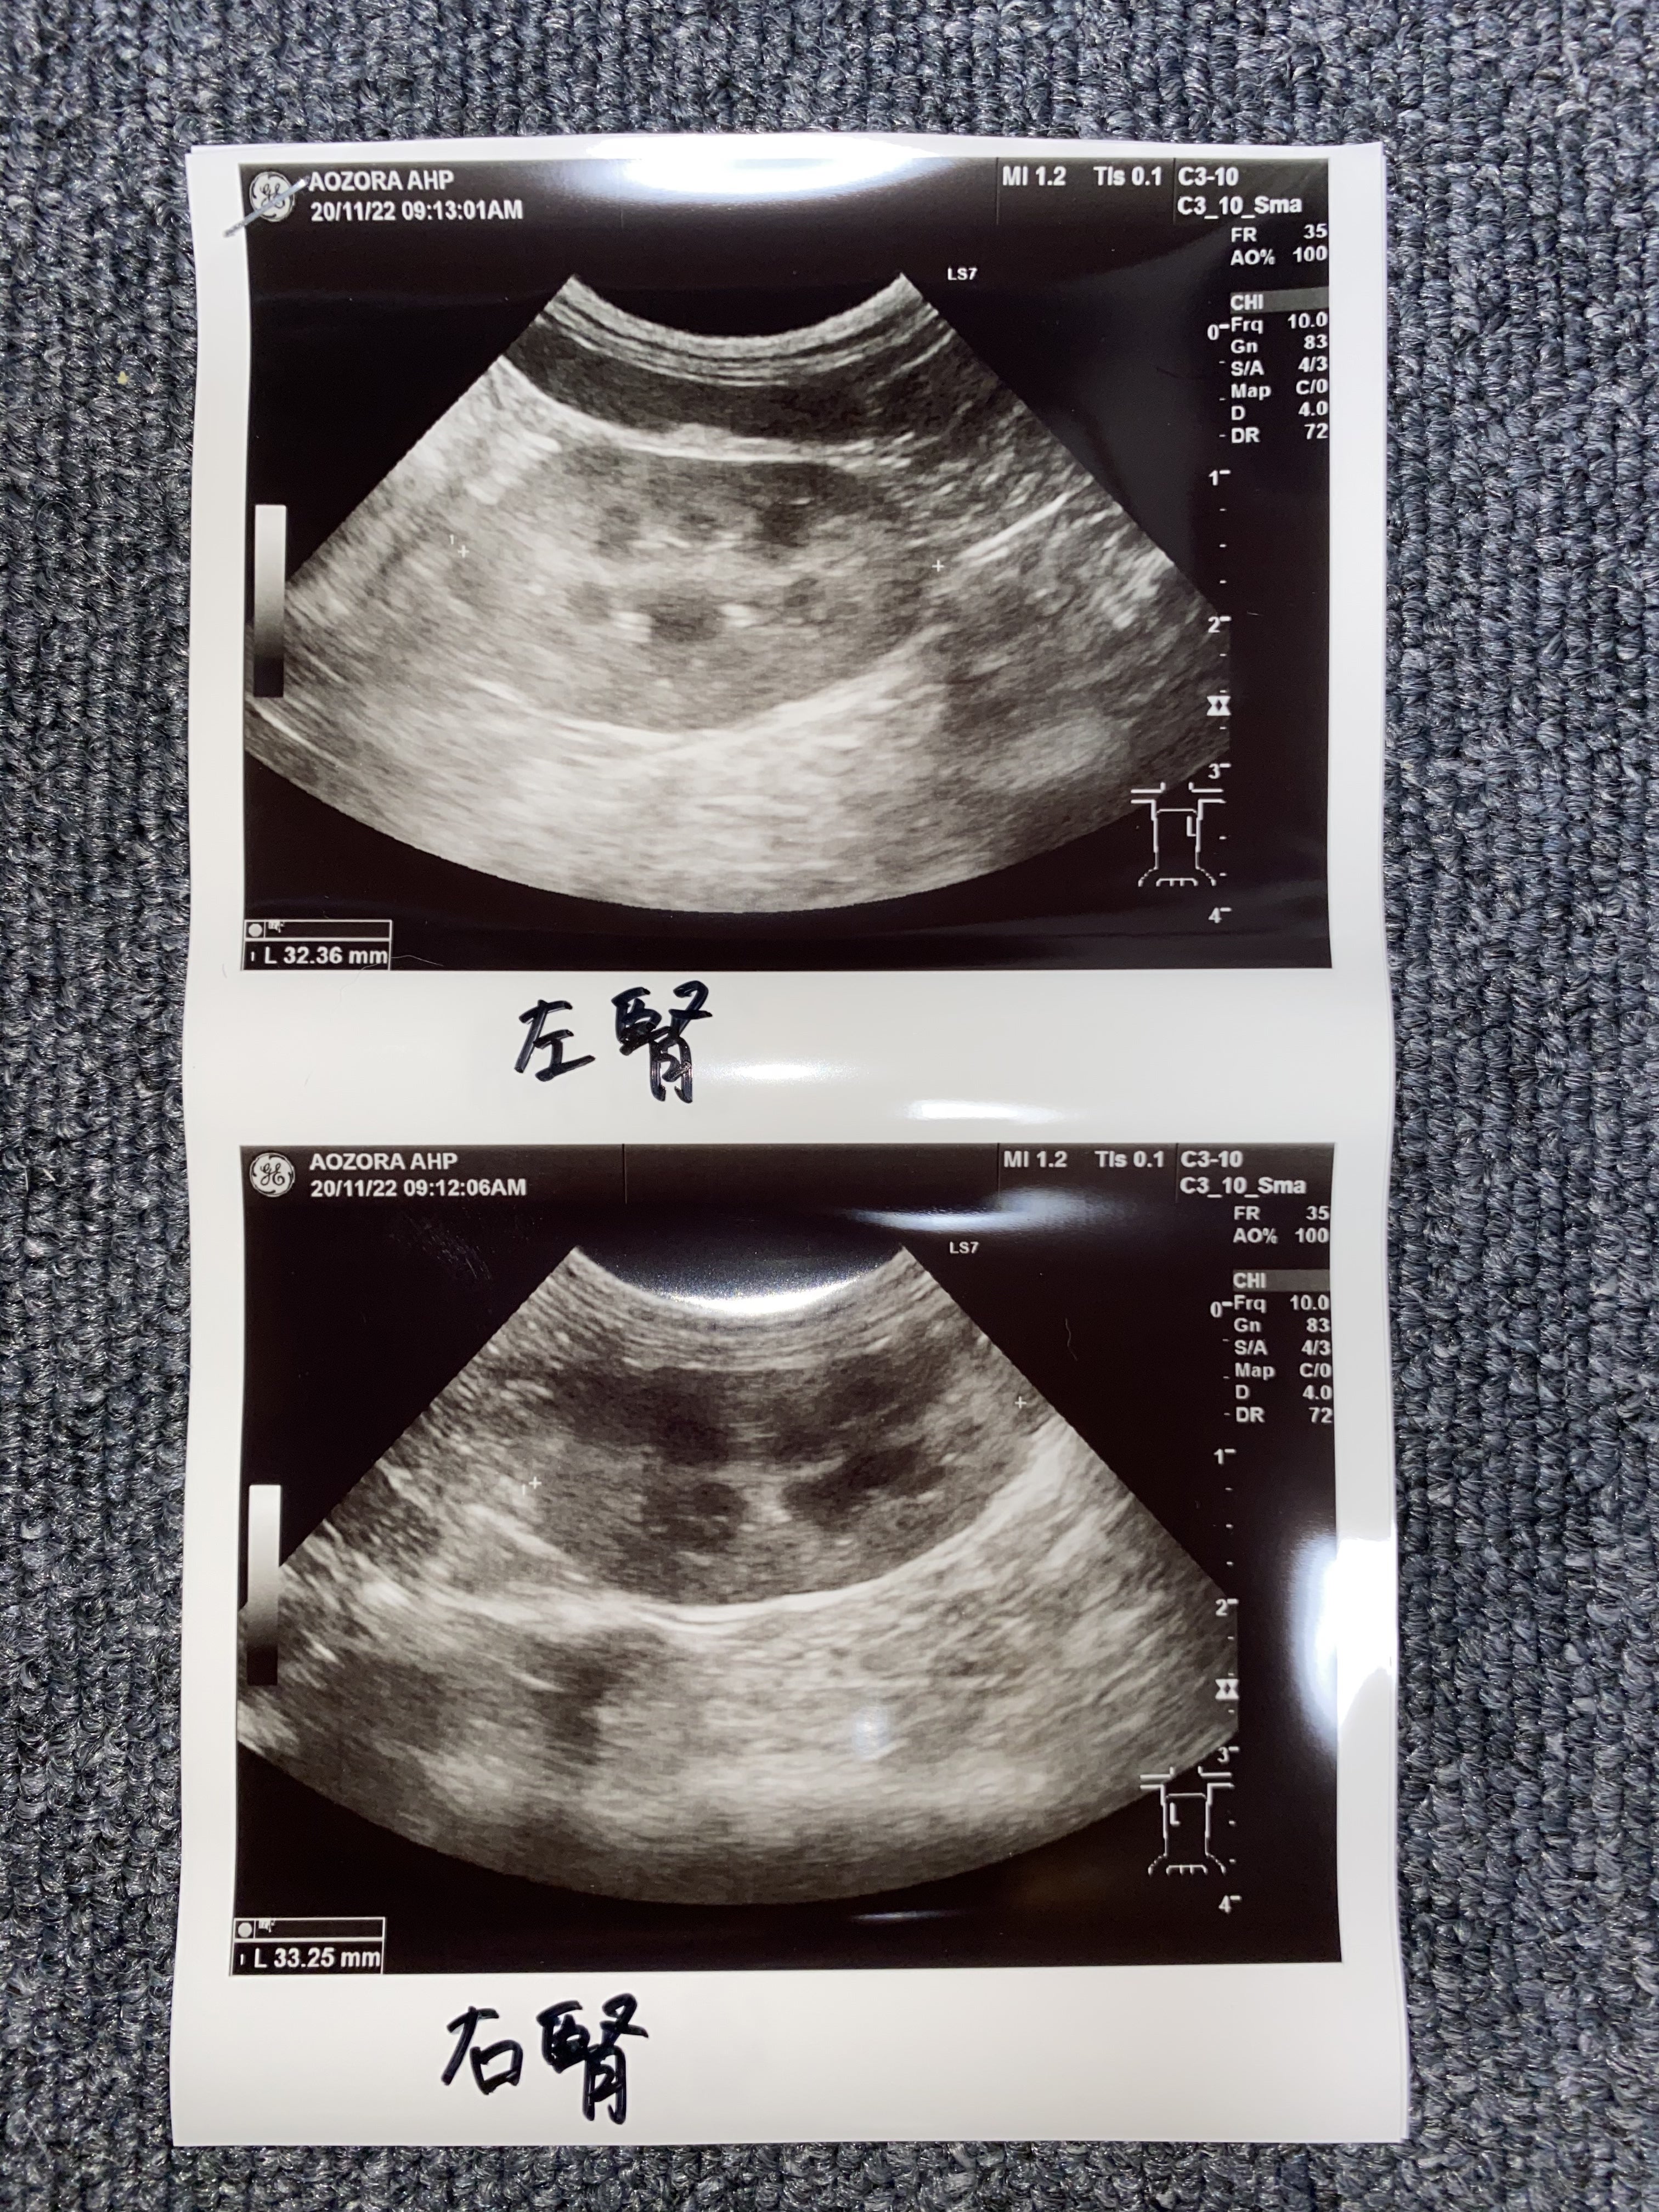

エコー検査も綺麗で問題ないそうです。